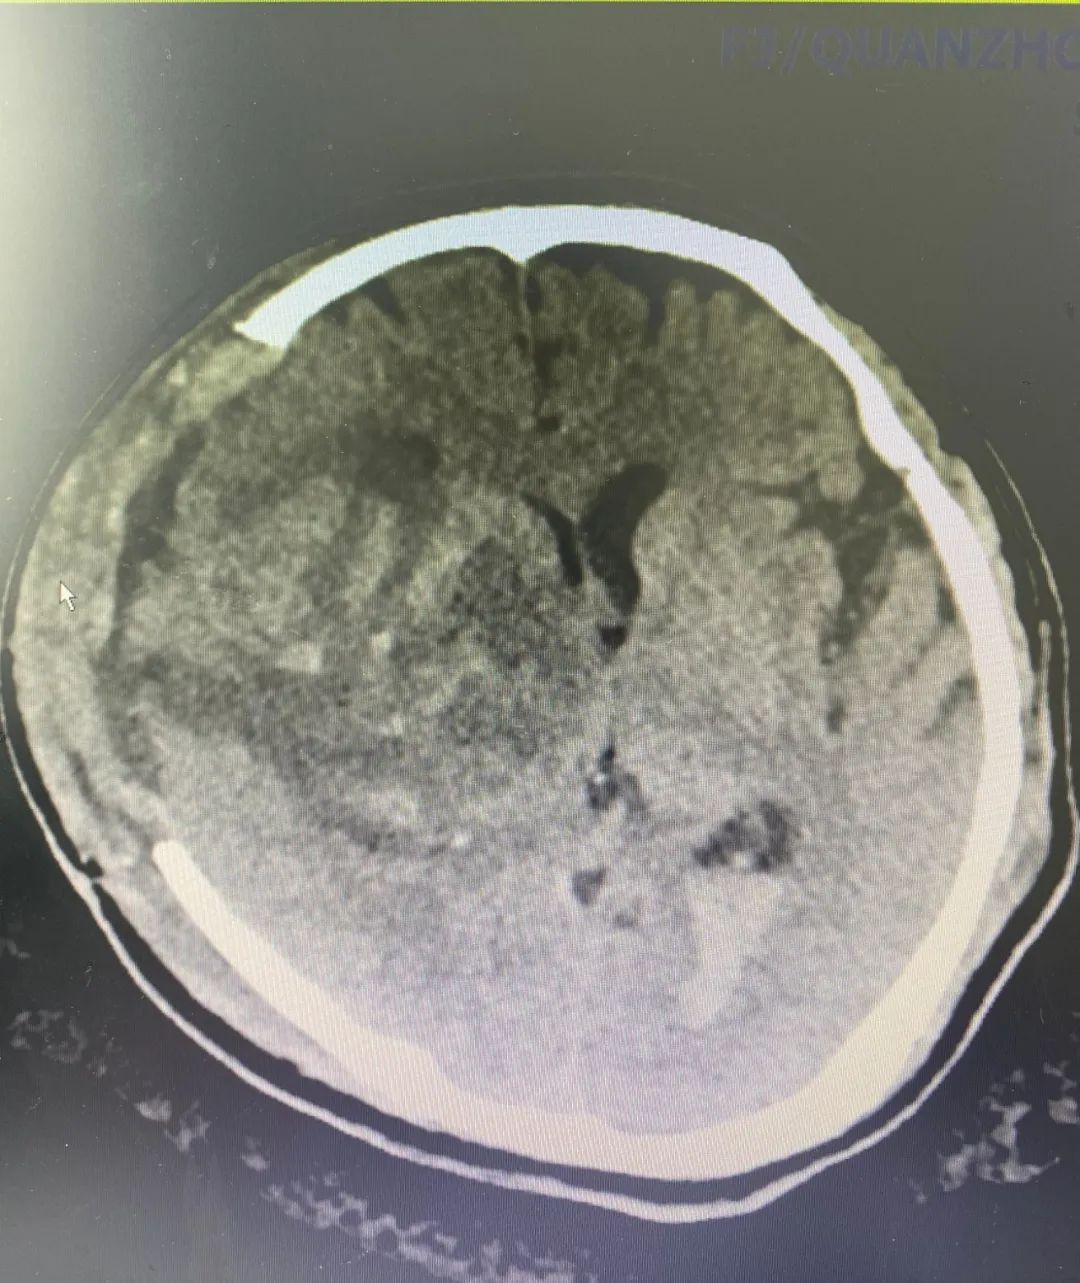

患者劉先生,6月下旬在出現(xiàn)突發(fā)言語含糊、左側(cè)肢體無力癥狀1小時(shí)后,求診于我院急診科,查顱腦CT提示右側(cè)基底節(jié)出血。急診科及時(shí)給予止血、預(yù)防應(yīng)激等處理,并經(jīng)我院神經(jīng)外科醫(yī)師會(huì)診后,根據(jù)頭顱CT所示,右側(cè)基底出血量約7ml,周圍腦溝腦回、右側(cè)側(cè)腦室部分受壓,中線居中,環(huán)池清楚,腦室無明顯擴(kuò)大,且神志清楚,能夠?qū)Υ穑催_(dá)到手術(shù)指征。醫(yī)生將此情況告知家屬,建議暫時(shí)予以保守治療,家屬表示理解和接受,劉先生入住接受治療。

▲術(shù)前、術(shù)后CT對(duì)比

入院后1小時(shí)左右,劉先生嘔吐胃內(nèi)容物2次,意識(shí)障礙較前加深,遂予以查體見神志處于昏睡狀態(tài),右側(cè)瞳孔呈圓形,直徑約4.0mm,對(duì)光反射遲鈍,考慮腦出血增加,予急查CT提示右側(cè)基底節(jié)出血量較前增加,約130ml,周圍腦溝腦回、右側(cè)側(cè)腦室受壓;環(huán)池變窄,腦干受壓,再次查體見右側(cè)瞳孔呈圓形,直徑5.0mm,對(duì)光反射消失,左側(cè)瞳孔呈圓形,直經(jīng)約4.0mm,對(duì)光反射遲鈍,考慮腦疝形成,立即予以20%甘露醇250ml靜滴脫水降顱壓。